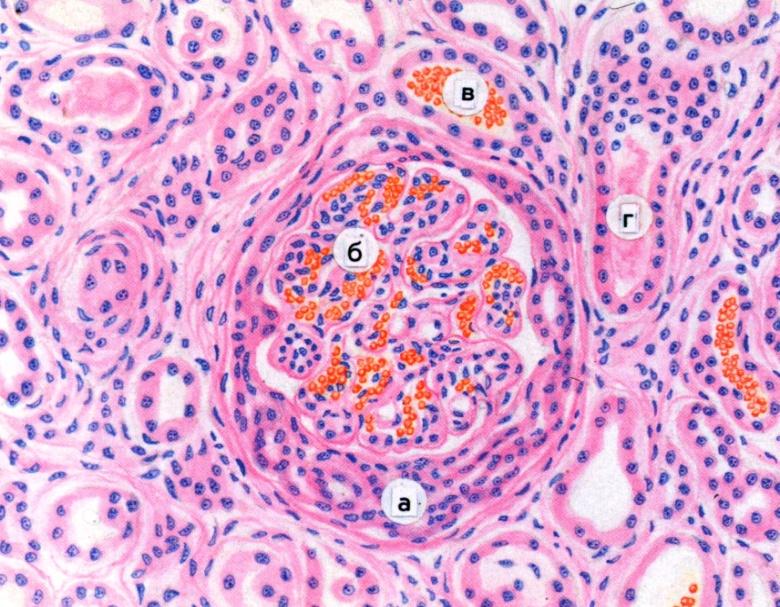

Механизм остро го диффузного гломерулонефрита